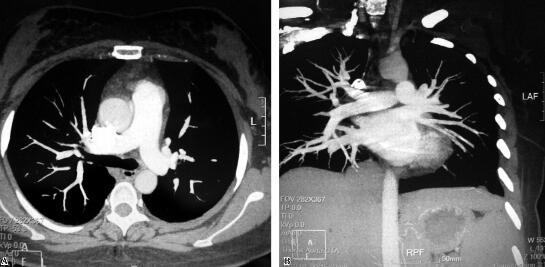

随访半年,患者无血栓复发倾向,无不适症状及阳性体征,复查肺动脉CTA示:肺动、静脉栓塞均消失(图2),仅残留下肢深静脉血栓。

图2